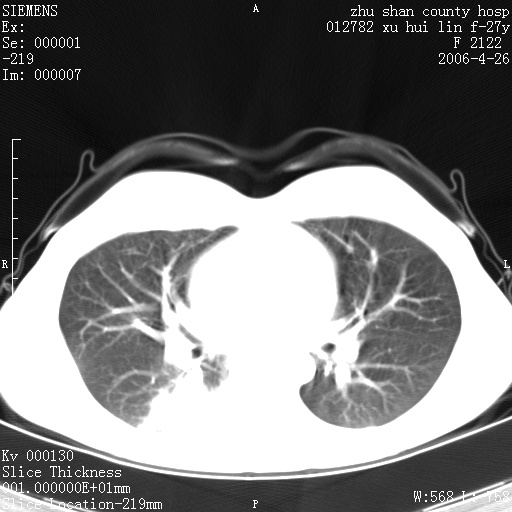

女性 病人 27岁!本院职工家属,五月前因感冒透视发现病变,ct示:左肺下叶背段感染性病变。经过半月规范抗生素治疗后复查病变无明显变化,后行四月规范抗痨治疗,复查无明显变化,后复查无效!请大家帮忙看看!

右肺下叶背段见片状高密度区,边界不清,密度不均,无钙化及空洞影,背段支气管通畅。所见层面肺门及纵隔内未见明显肿大淋巴结影。

女性 病人 27岁!本院职工家属,五月前因感冒透视发现病变,ct示:左肺下叶背段感染性病变。经过半月规范抗生素治疗后复查病变无明显变化,后行四月规范抗痨治疗,复查无明显变化,后复查无效!

诊断:首先还是考虑为慢性炎症。

从战友提供的ct图象及定位图象看应该是间质性炎症改变.如果患者不放心可建议她行纤支镜检查.

局灶机化性肺炎可能,建议她行纤支镜检查